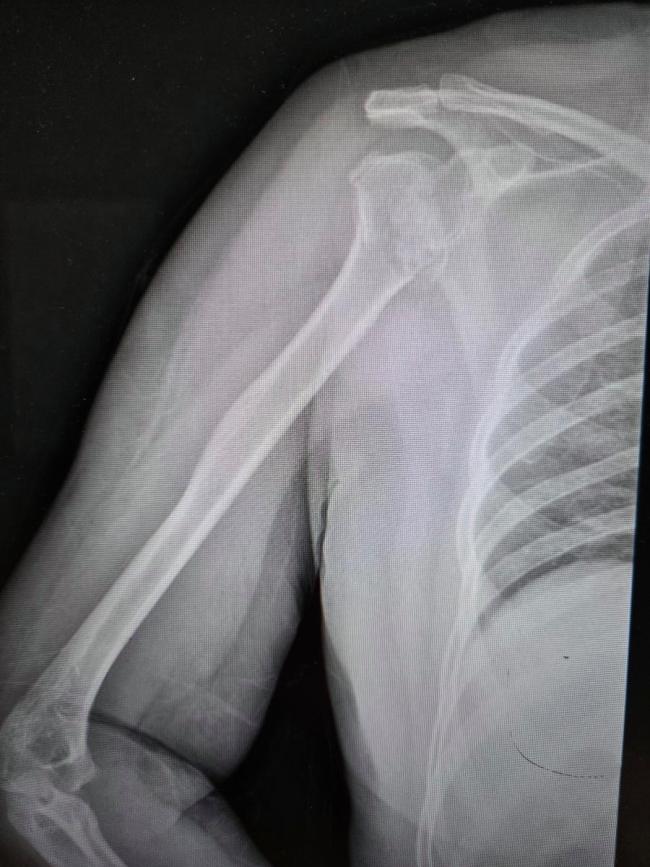

送医后的CT检查结果显示:右肱骨近端四部分粉碎性骨折,且伴有罕见的肱骨头后脱位。她的肩膀碎成了七八块,而且关节位置发生了严重偏移。由于手术难度极大,她被紧急转诊至河南省人民医院。

负责接诊的创伤骨科刘涛主任表示,这是他从业多年见过最蹊跷的病例之一。“没喝酒、没摔下床,就在被窝里躺着,肩膀怎么可能碎成这样?”骨科专家组会诊后,决定放弃简单的“换关节”,通过高难度的手术为她“拼”回原装关节。

在排除了肿瘤破坏骨质、严重骨质疏松后,刘涛主任盯住了一个细节——肩关节后脱位。肩关节后脱位相当罕见,在所有肩关节脱位中不到4%,而它最常见的诱因就是癫痫发作。前脱位很常见,但后脱位需要非常大的暴力才能造成。